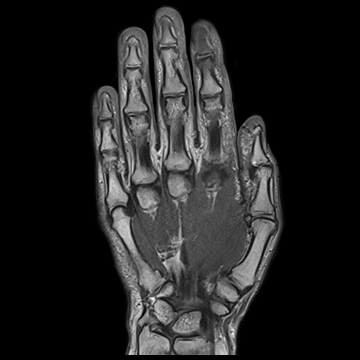

手・指関節

PD TSE,

PD TSE SPAIR,

T1 TSE

TNATIVE SPACE非造影